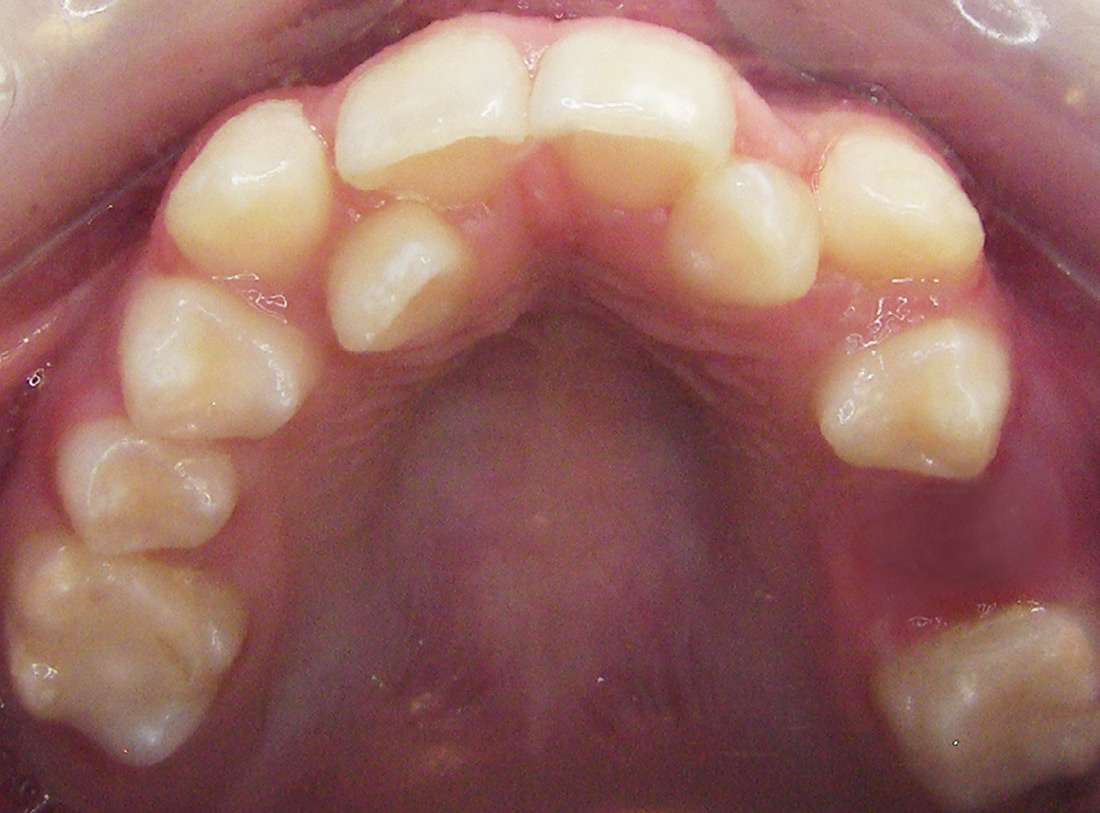

Case Studies

We’re proud of our patients’ new smiles, and most times, they’re even more proud to show them off. You’ll be ready for your close-up, too, once you visit the friendly experts at LB Orthodontics. Click here to see our smile gallery.